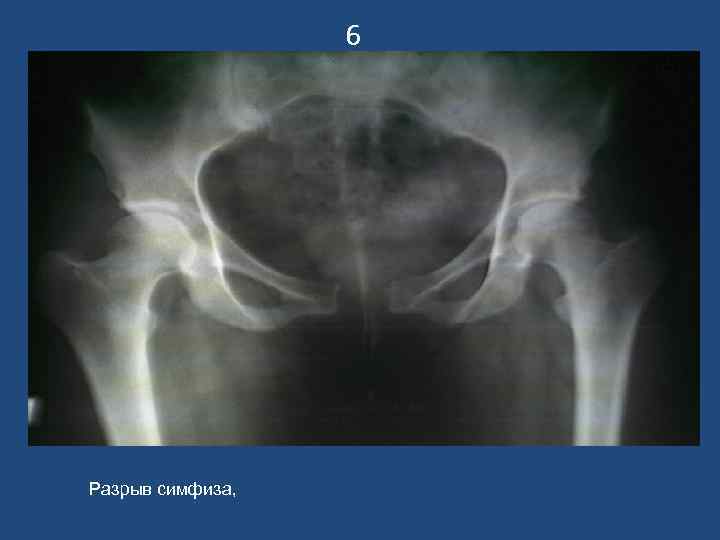

6 Разрыв симфиза,